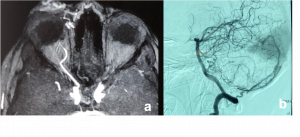

Orbital and Eyelid Arterio-Venous Malformation a) Magnetic Resonance Angiography TRICKS (Time-Resolved Imaging of Contrast KineticS) confirms mid and delayed arterial phase blushing of orbital and eyelid mass with dense contrast. b) Digital Subtraction (DSA) images of right orbit showing large dural AVM with the engorged external carotid artery and its branches and early venous drainage. | |